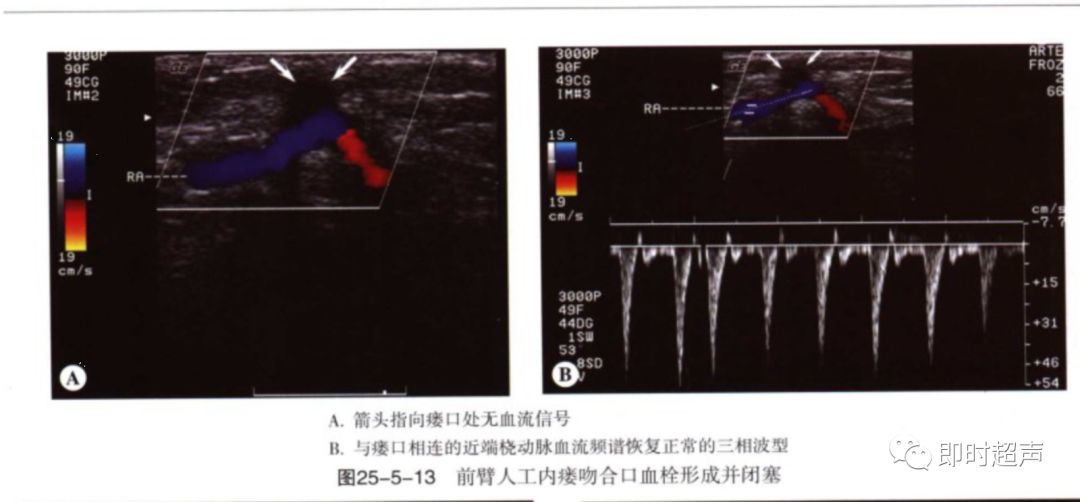

血栓:血栓与狭窄密切相关,常发于静脉侧,静脉管腔压瘪可除外血栓形成。闭塞处可见彩色多普勒血流中断,频谱多普勒信号消失。流入道动脉呈高阻频谱改变。

狭窄:狭窄大多发生于吻合口及静脉流出道。

超声表现:多普勒分析:狭窄处直接征象:PSV>4m/s(直径狭窄率50%以上),间接征象:供血动脉或肱动脉呈高阻波形,血流量减少。